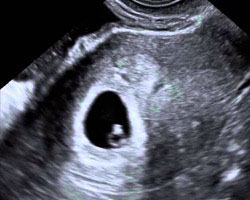

Já sabes que esta é uma semana fulcral, na qual acontece a conceção. Queres ver a imagem da ecografia correspondente? Aqui a tens!

Ecografia da 3ª semana

É o que se denomina de falso negativo. Durante a terceira semana de gravidez também é demasiado cedo para detetar qualquer sinal de conceção através de uma ecografia.